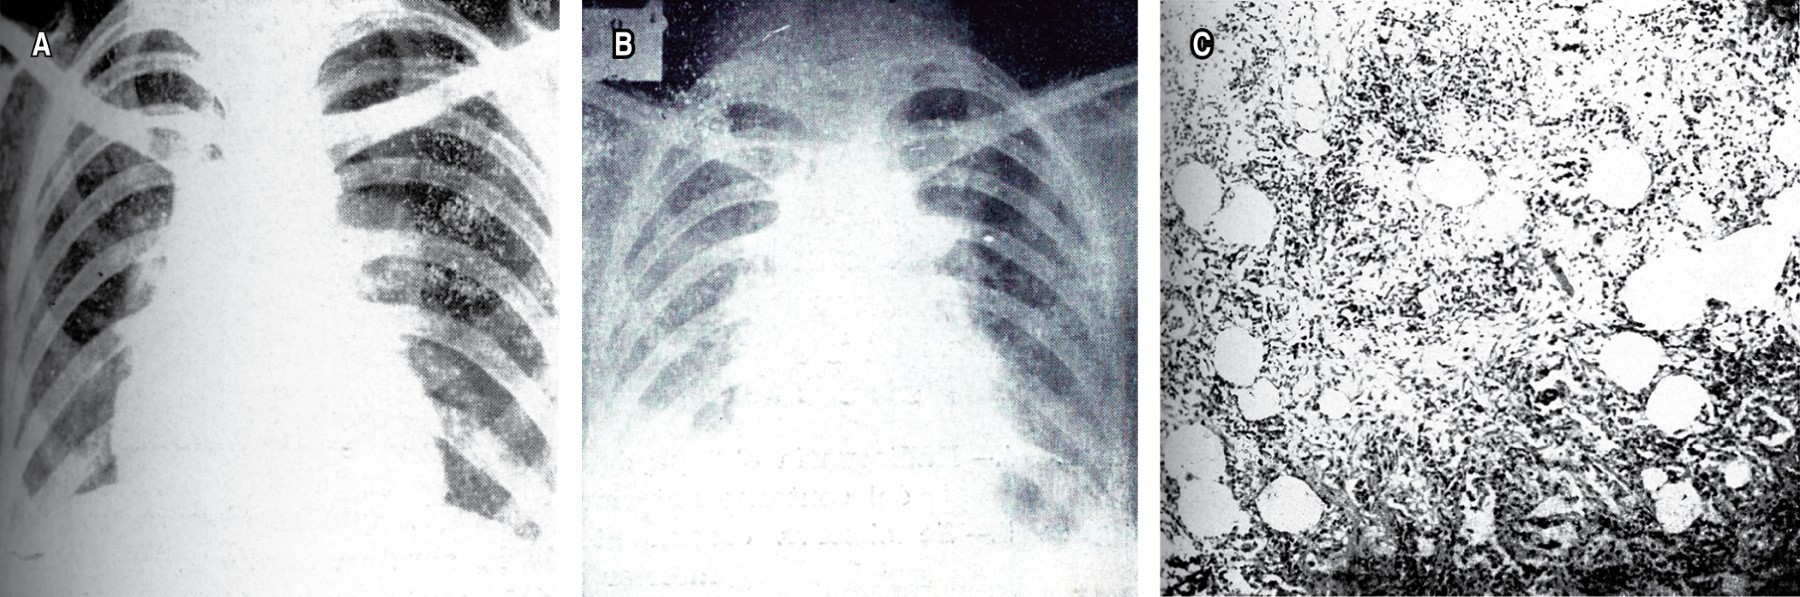

.Las enfermedades pulmonares intersticiales difusas (EPID) han sido siempre un enigma para el personal médico; se debe en parte a la variedad de etiologías relacionadas con ellas, así como a los cambios histopatológicos que se reportan en las biopsias o autopsias y los escasos datos, clínicos o de las pruebas funcionales respiratorias, que comparten todas ellas. Las primeras publicaciones sobre fibrosis pulmonar difusa en NCT (Revista Mexicana de Tuberculosis) corresponden a dos casos descritos con detalle en el aspecto clínico y en sus características anatomopatológicas de autopsia. El primero de ellos data de 1956 y se titula: "Fibrosis pulmonar intersticial difusa" del Dr. F. Marroquín de la Unidad de Patología de la Escuela de Medicina de la UNAM, en el Hospital General de México.1 El segundo caso fue publicado en 1961: "Fibrosis intersticial difusa. Caso clínico-patológico", por los doctores José Vargas de la Cruz, Enrique Milán Reyes y Arturo Tinoco Hernández del Servicio de Anatomía Patológica del Hospital de La Raza del IMSS.2 Desde entonces y en ambas publicaciones, los autores destacan la poca correlación entre los datos clínicos y los cambios macro y microscópicos (Figuras 1 y 2), más aún, la variabilidad en edades, lo avanzado de los casos al momento del diagnóstico y la falta de asociación con las causas conocidas de la enfermedad, por ejemplo, las exposiciones ambientales o las infecciones, así como la nula respuesta a los tratamientos implementados; todo esto incrementaba la incertidumbre ante estas enfermedades.